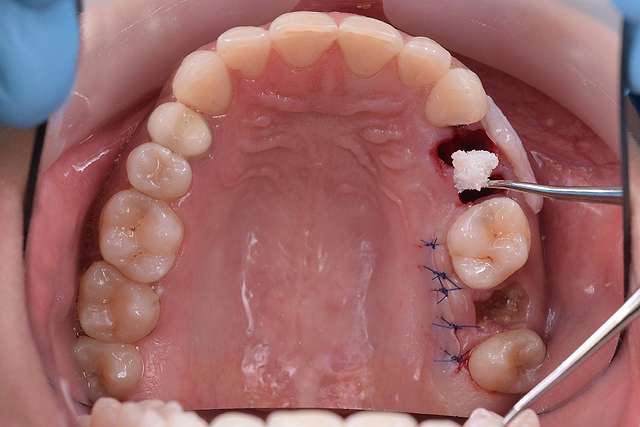

Guided surgery, for one, facilitates an ideal pre-planned position, in relation to available bone, and even more important, in relation to the future implant supported crown. Guided surgery translates into increased precision, which means safer surgeries, reduced surgery time, and reduced trauma. Also the focus of these types of treatments is shifted towards tissue reconstruction, which on the long run, has a far greater impact esthetically and biologically. Tissue stability means implant longevity. This case is a relevant example for this type of approach towards implant dentistry.